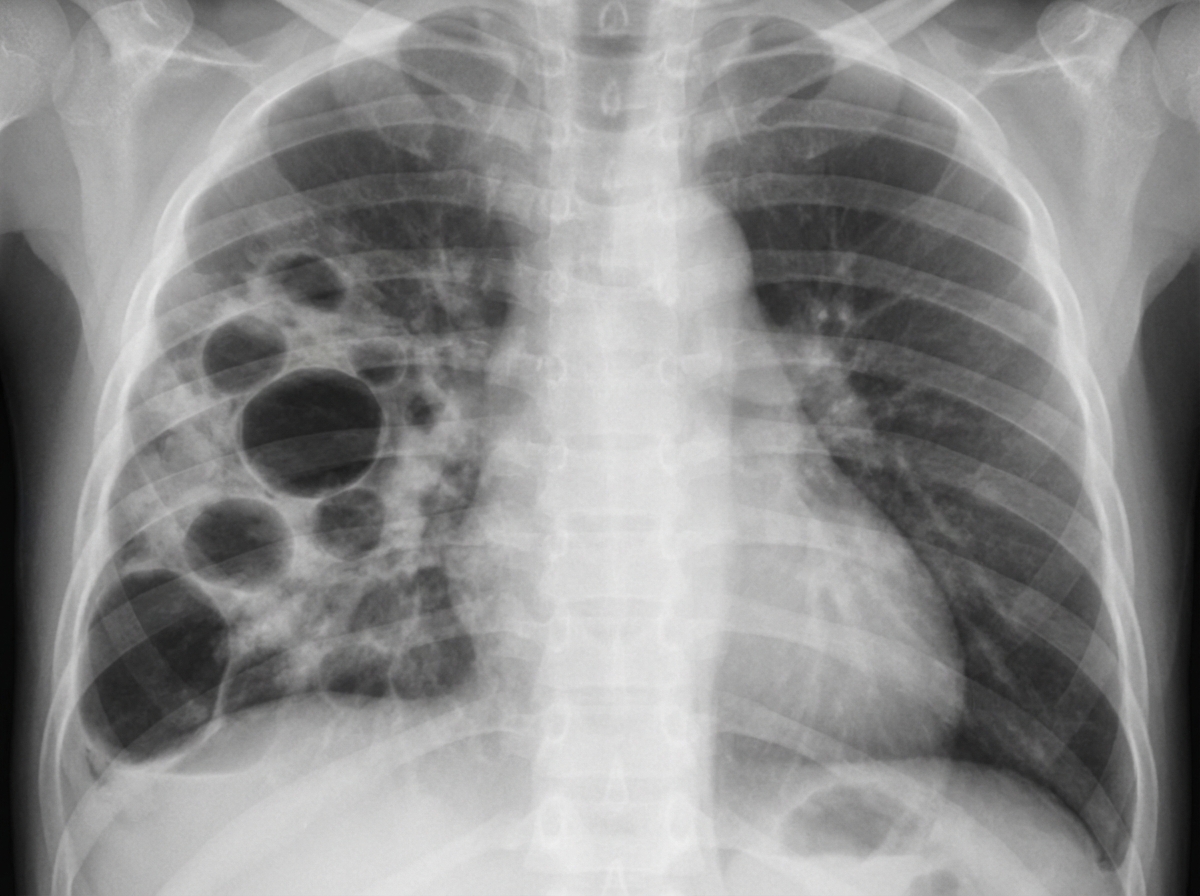

An infant presented to OPD with features of respiratory distress. The X-ray is shown below. The most probable organism is?

Explanation: ***S. aureus*** - **Pneumatoceles** (thin-walled air cysts) on chest X-ray are **pathognomonic** for staphylococcal pneumonia in infants. - S. aureus commonly causes **necrotizing pneumonia** with **cavitation** and **pneumothorax** formation in pediatric patients. *S. pyogenes* - Typically causes **pharyngitis** and **cellulitis** rather than severe pneumonia with cavitary lesions. - Chest X-ray findings usually show **lobar consolidation** without pneumatoceles or cavitation. *Klebsiella* - Commonly affects **immunocompromised adults** and causes **upper lobe consolidation** with **bulging fissures**. - Rarely causes **pneumatoceles** in infants; more associated with **thick, bloody sputum** production. *E. coli* - Primarily causes **neonatal sepsis** and **meningitis** rather than primary pneumonia in infants. - When it causes pneumonia, it typically presents as **diffuse infiltrates** without characteristic pneumatocele formation.